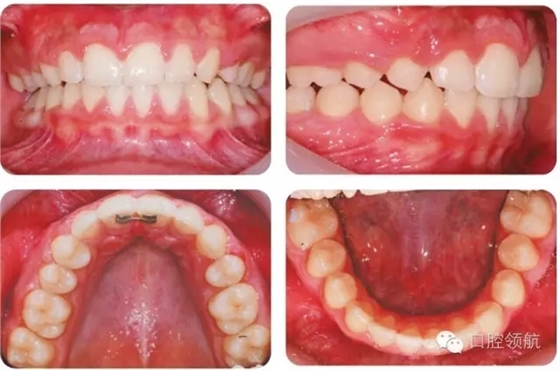

UR4改形受到休息和功能狀態(tài)時(shí)上唇位置和上前牙外觀影響。休息時(shí)上唇線較低,切緣暴露很少,這樣齦緣高度不一致的情況不必特別考慮。因?yàn)榈谝磺澳パ澜h(yuǎn)中徑小于尖牙,托槽應(yīng)略靠遠(yuǎn)中使牙齒近中腭側(cè)旋轉(zhuǎn)。為了使前磨牙伸長(zhǎng),托槽應(yīng)放置在臨床牙冠中心略偏齦方,使頰尖位置與對(duì)側(cè)尖牙協(xié)調(diào)。如果伸長(zhǎng)前磨牙導(dǎo)致咬合早接觸,應(yīng)適當(dāng)降低舌尖。如果笑線較高,應(yīng)考慮壓入第一前磨牙或外科修整齦緣高度。前磨牙可以進(jìn)行貼面以更好地模擬尖牙外觀,調(diào)整牙尖垂直位置。圖2.45為最后的咬合像。

來(lái)源于口腔領(lǐng)航